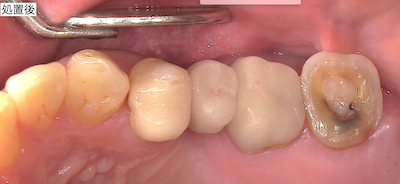

治療前後の比較です。

患者さんはとても喜んで下さったので、良かったです。